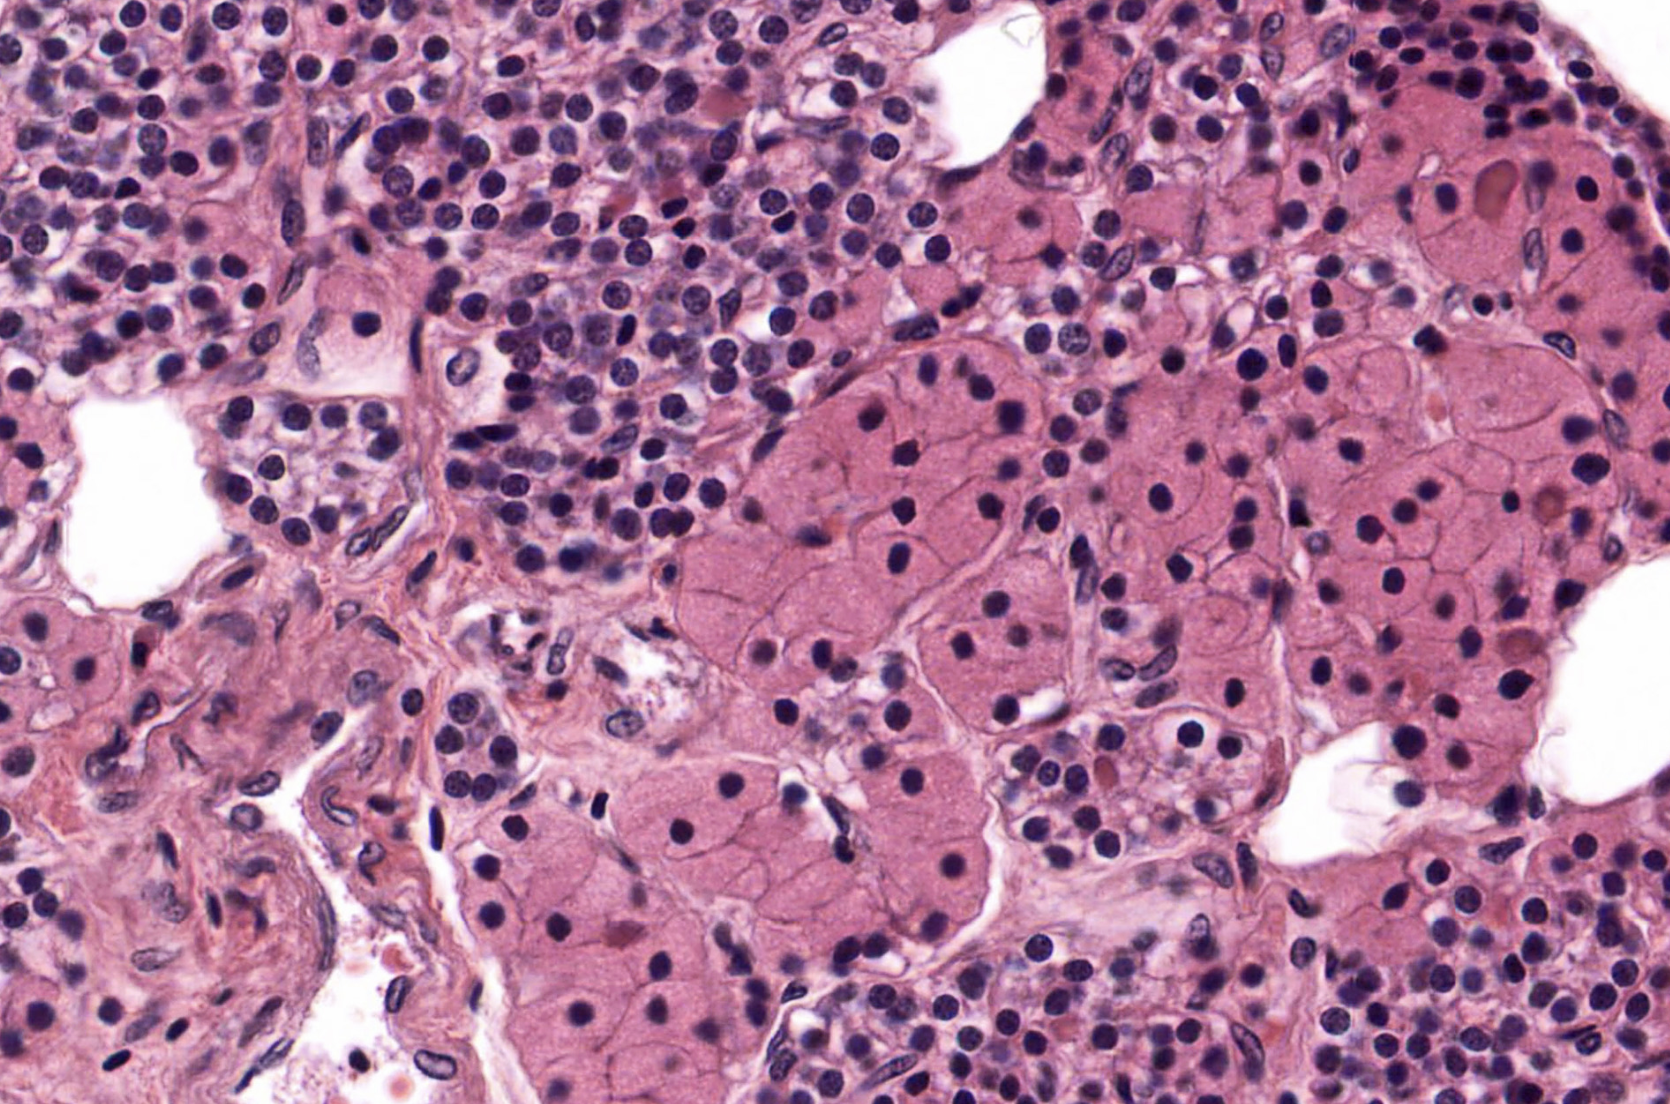

pancreatic islet

adrenal gland